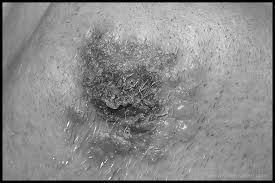

Herpes simple

Es la lesión que aparece en la región de la boca entre la piel y el borde del labio, se caracteriza por un grupo de vesículas sobre una base enrojecida, también puede aparecer en el borde de la piel y los labios vaginales o entre el borde de los labios vaginales y la mucosa.

El cuadro clínico se caracteriza por ardor, comezón y dura aproximadamente una semana cuando se convierte en costra.